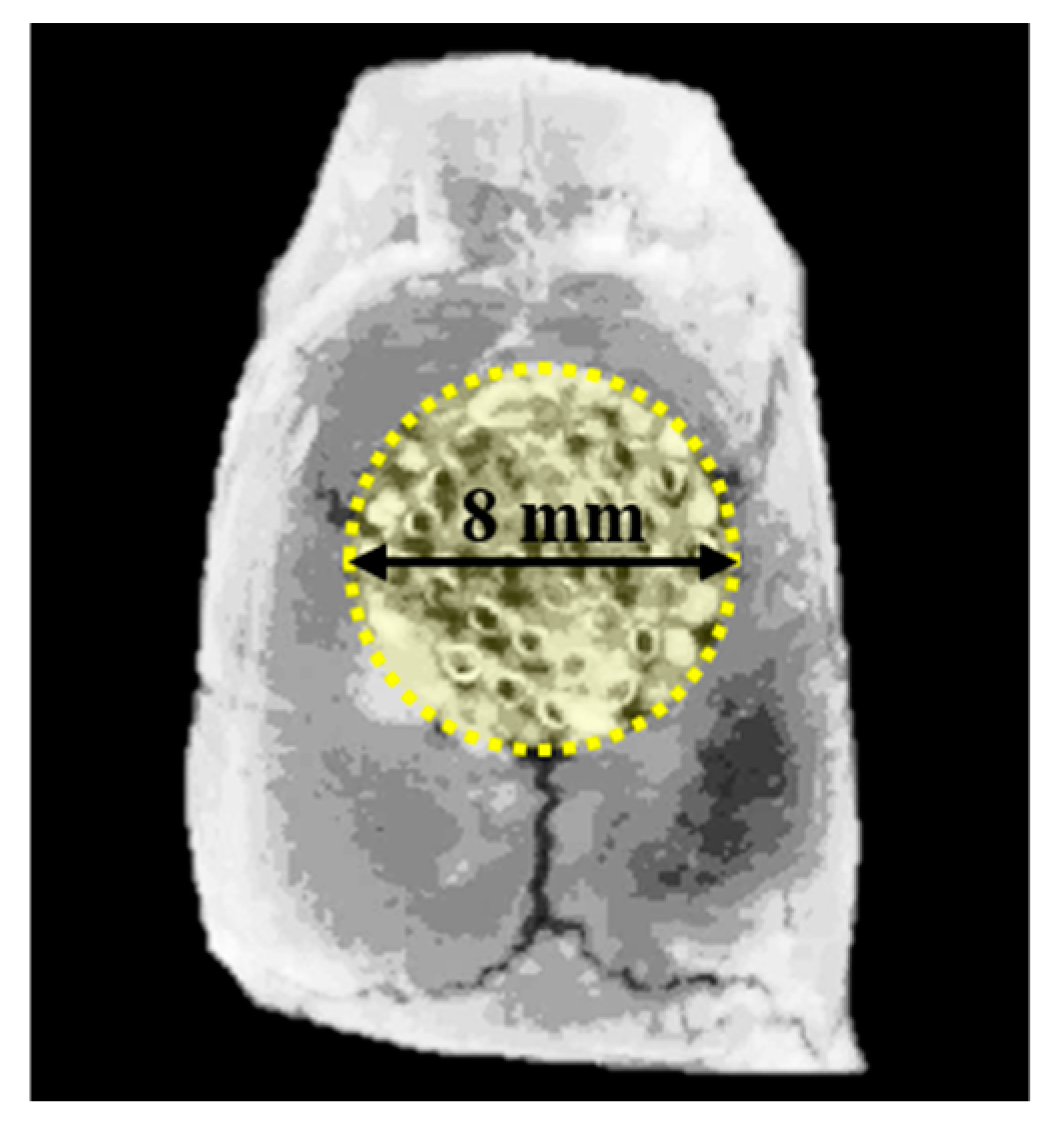

2.3.2. Surgical Procedures

2.3.3. Micro-Computed Tomography (μCT) Analysis